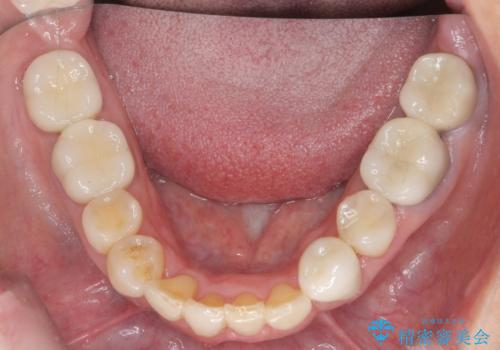

50代女性 八重歯を矯正治療 歯並びの中等度のがたつき

- 八重歯の矯正を希望されて来院。

歯は入りきらないため、通常の抜歯矯正を行いました。

歯がご年齢的に動きにくいため、被せ物のやり替えを含めて治療期間の短縮を図りました。

矯正治療自体は2年半、虫歯治療等で1年ほどかかっています。